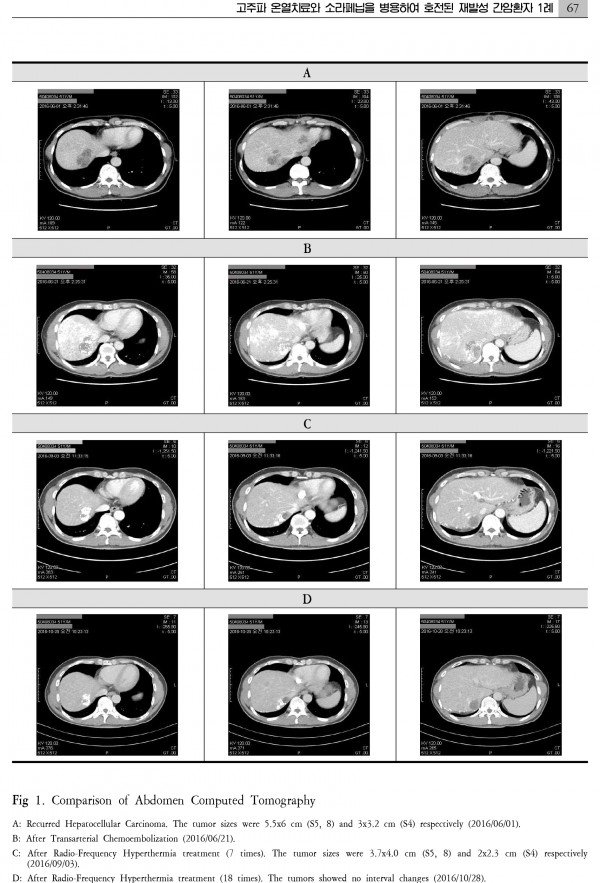

간암 치료 대전대학교 논문

간암치료 케이스논문 대전대학교논문최종.pdf